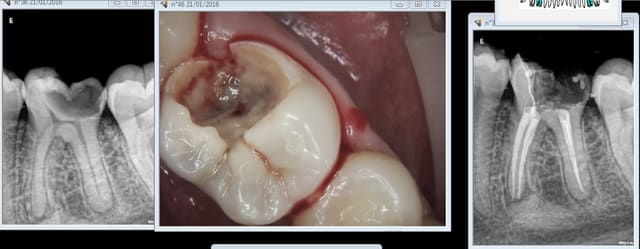

Ici reprise de carie sous composite à 99,9 % pas fait sous digue.

> Ici reprise de carie sous composite à 99,9 % pas fait sous digue.